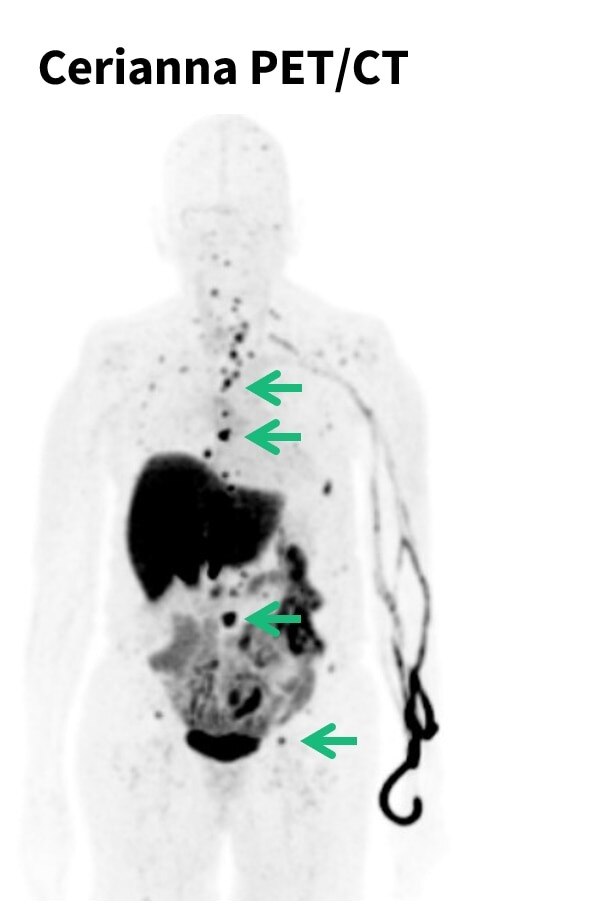

Cerianna PET/CT

Download